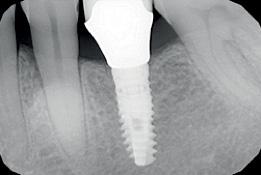

An orthopantomogram (OPG) revealed RL8 and LL8 were mesioangularly impacted and their roots were crossing both upper and lower white lines of the inferior alveolar canal (IAC). LL8 roots showed darkening of root at the level of IAC (Fig 1).

It was decided to request a Cone Beam CT to substantiate findings of the routine OPG in relation to the IAN.

CBCT revealed the following findings:

LL8: IAC was running buccal to roots of LL8 which had 3 roots (Fig 2).

RL8: IAC was seen running between the buccal root which was hooked mesially and lingual roots at its apex, vulnerable to surgical injury (Fig 3).